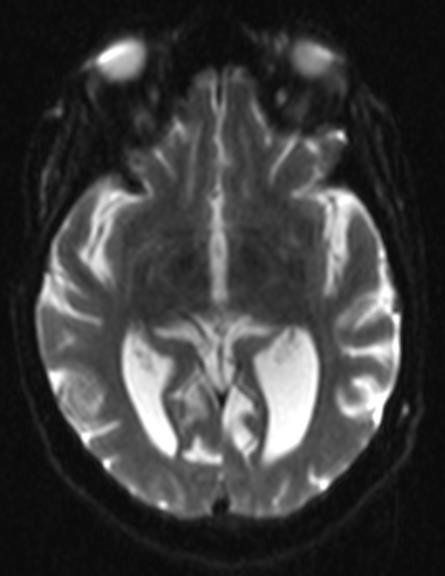

É comumente visto na RNM como áreas de aumento simétrico de sinal T2 / FLAIR envolvendo os corpos mamilares, tálamo dorsomedial, placa tectal, área periaquedutal e ao redor do terceiro ventrículo.

T2 / FLAIR: intensidade de sinal simetricamente aumentada nos:

-corpos mamilares

-tálamo dorsomedial

-placa tectal

-substância cinzenta periaquedutal

-em torno do terceiro ventrículo